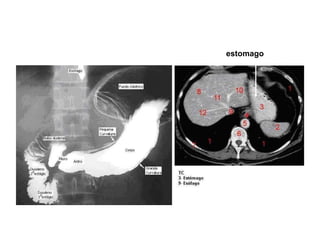

Estomago Características gerais P arte mais dilatada do trato gastrointestinal Possui formato em forma de “J” L ocalizado  Regiões epigástricas, umbelical e hipocôndrio esquerdo entre a parte abdominal do esofago e o intestino delgado

Localização do estomago entre o esofago e o intestino delgado

estomago